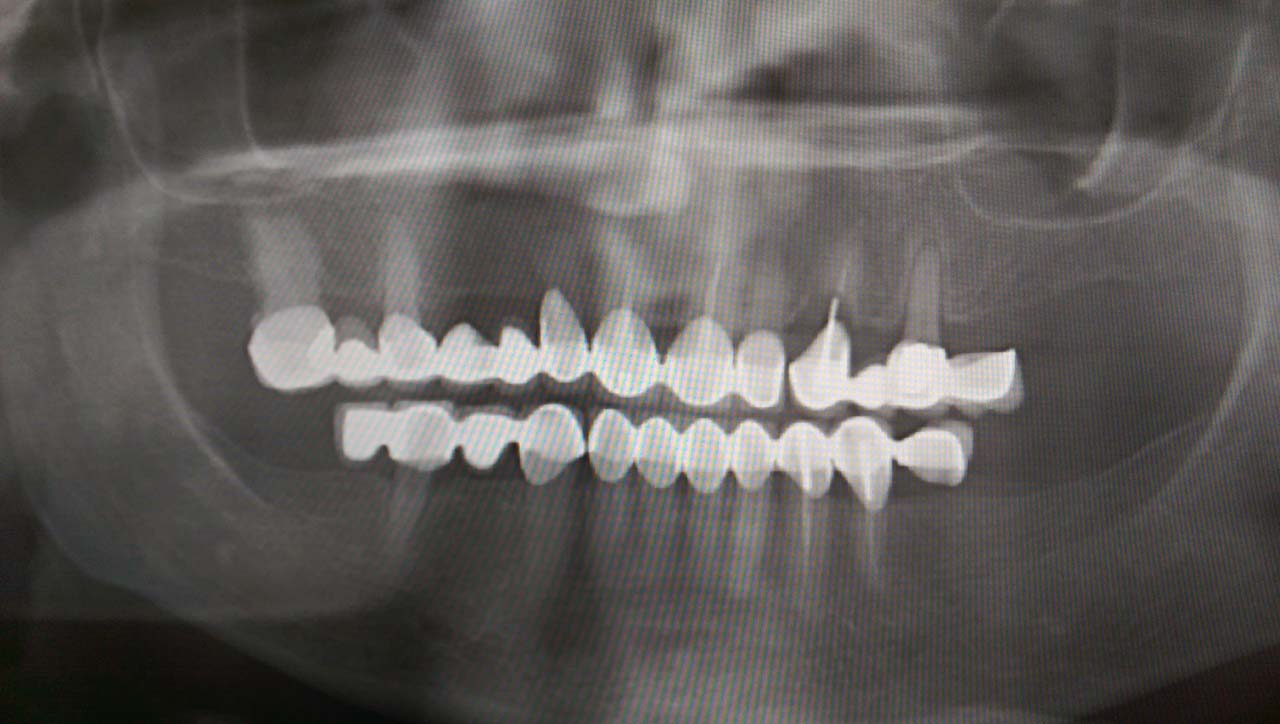

Alsó állcsont teljes rehabilitációja 72 óra alatt

Alsó állcsont teljes rehabilitációja 72 óra alatt, azonnal terhelhető implantátumokkal súlyos paradontitisben szenvedő dohányzó páciens esetében. Az alsó állcsont fogai mind mozogtak az előrehaladott fogágypusztulás miatt.

A fogakat eltávolítottuk, a gyulladt, fertőzött csontot kitakarítottuk, kifertőtlenítettük, majd azonnal implantáltunk.

Svájci, IHDE márkájú, azonnal terhelhető implantátumokat helyzetünk be, és ezekre harmadnapra rögzített, hosszútávú, fémvázas, esztétikus műanyaggal leplezett hidat ragasztottunk be.

Ezt az ideiglenes hidat a sebek gyógyulása miatt használjuk, de tartóssága miatt véglegesként is használható. A legtöbb esetben, ahogy itt is, 6 hónap múlva porcelán hídra cseréljük, a teljes gyógyulás után.